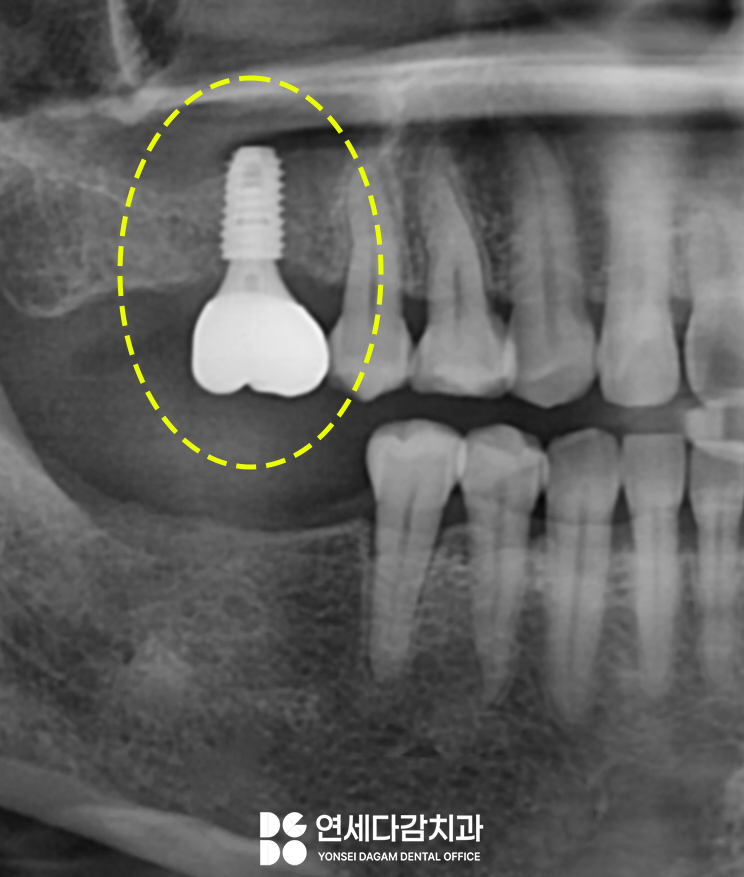

2주 정도 연조직 치유 후

최종 보철물을 제작하여

장착을 완료하였습니다.

맞은편 결손된 공간은

단순 식립을 통해

위아래 어금니 부위 모두

치료를 완료하였습니다.